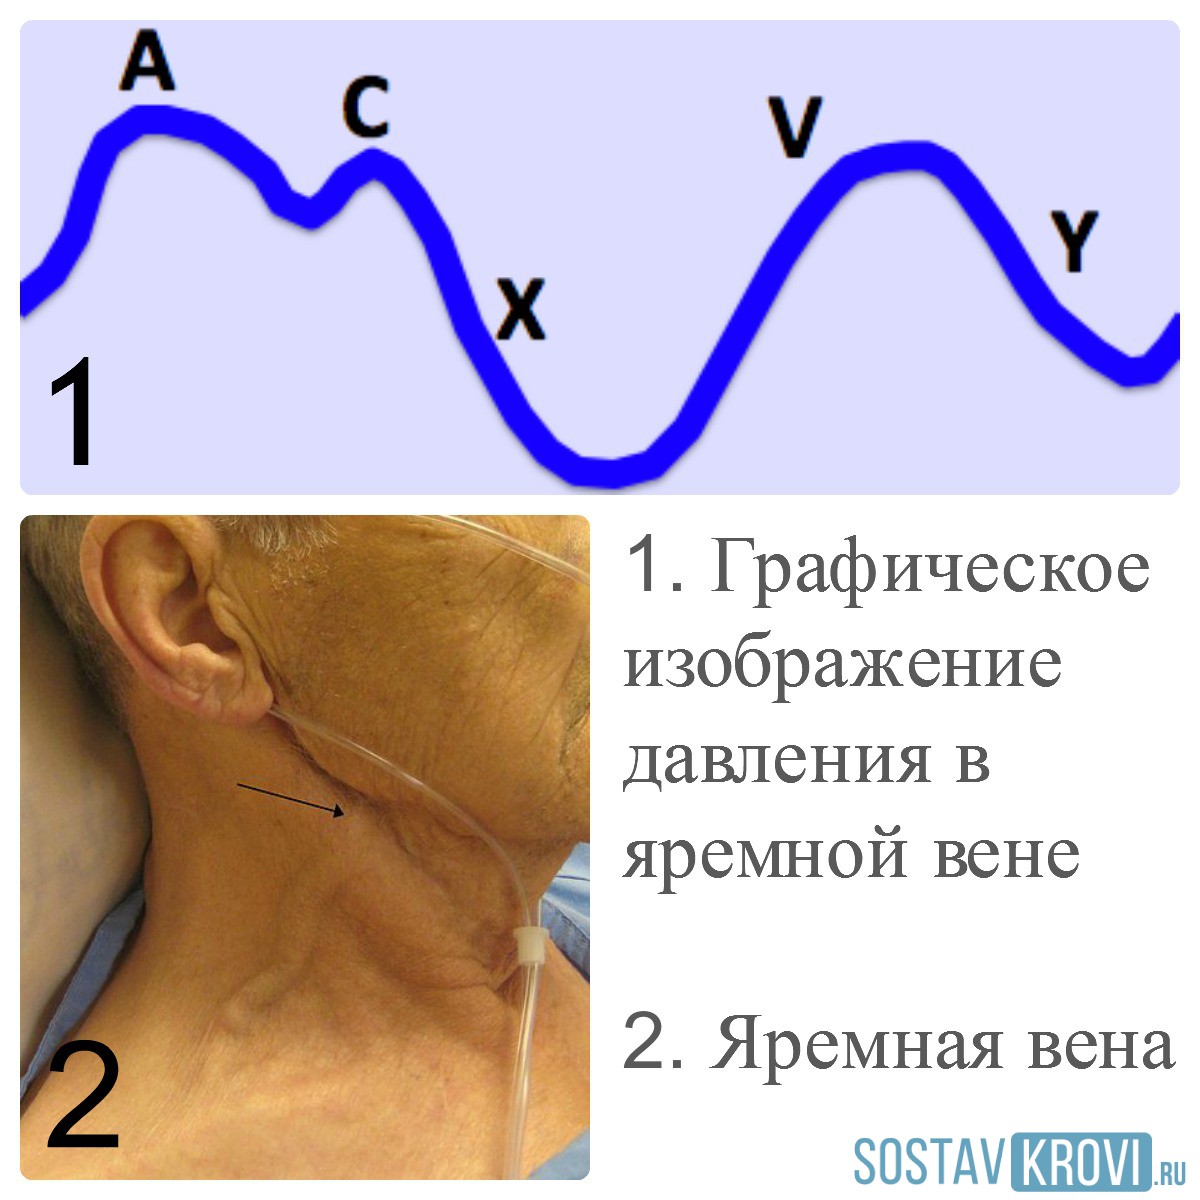

Анатомия внутренней яремной вены: КТ изображения